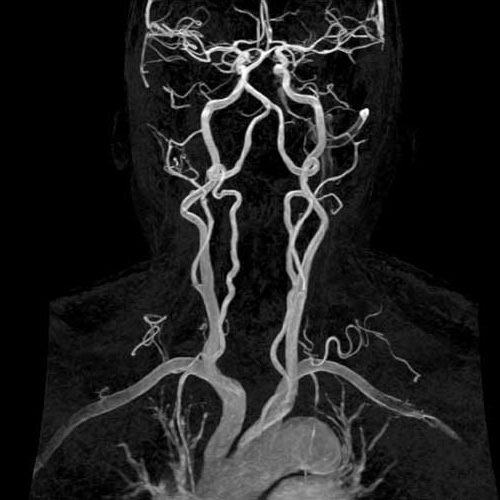

МРА артерій шиї Дослідження артерій шиї на МРТ або магнітно-резонансна ангіографія - це високоінформативний та безпечний метод, що дозволяє оцінити анатомічні та функціональні особливості кровоносного русла досліджуваної зони. Отримана в ході дослідження інформація дає можливість своєчасно призначити відповідне лікування і поліпшити прогноз патологічного процесу. Крім того, на підставі даних ангіографії можна провести планування оперативного втручання на судинах (стентування, ангіопластики). За допомогою ангіографії можна виявити:

МР ангіографію артерій шиї доцільно проводити без застосування контрастного препарату. |